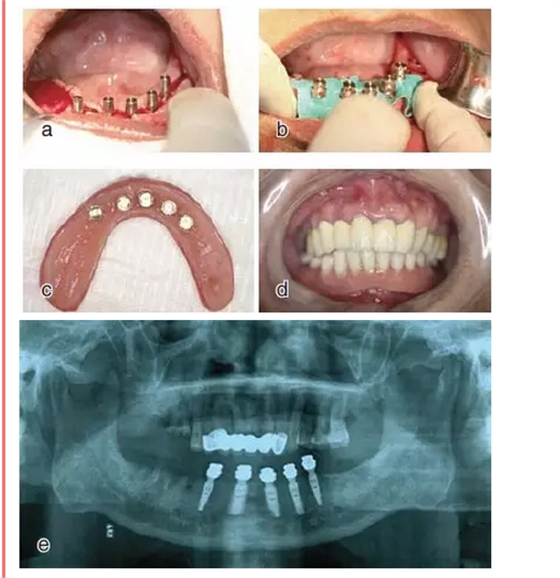

設(shè)計(jì)切口,剝離黏骨膜后,將截骨導(dǎo)板戴到骨面上,用咬骨鉗沿著截骨導(dǎo)板平面進(jìn)行截骨,并用骨銼修整骨平面,截骨完成后將種植導(dǎo)板固定在骨面上進(jìn)行種植備孔,完成后植入種植體。注意截骨平面要平整,否則影響種植導(dǎo)板的就位。

戴上套筒冠基臺(tái)進(jìn)行即刻修復(fù)。注意不是所有植入的種植體都可以進(jìn)行即刻修復(fù),醫(yī)師可以通過扭力值并結(jié)合ISQ松動(dòng)度測量值來選擇修復(fù)的種植體。

圖18

進(jìn)行即刻修復(fù):a.戴上基臺(tái);b.在基臺(tái)上戴入套筒冠;c. 套筒冠固位到原有義齒上;d.患者戴上有套筒冠的覆蓋義齒;e.

即刻修復(fù)完成后曲面體層片